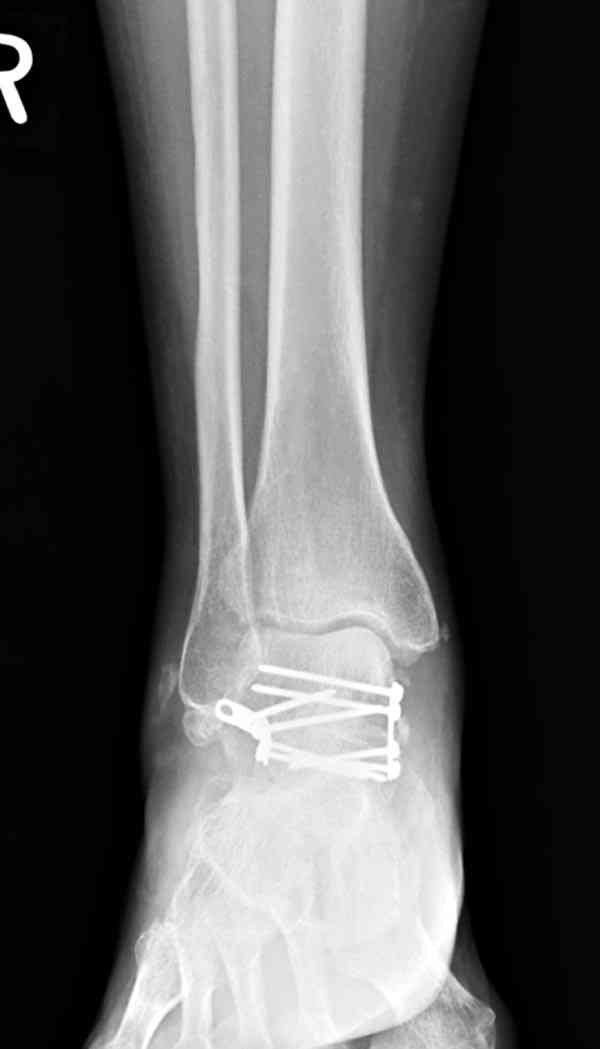

Случай с множественным оскольчатым переломом тарана оперированный из двойного доступа.

Через 2 мес.:

Через 8 мес.:

Через 14 мес.:

Два фрагмента суставной поверхности тарана можно восстановить боковой компрессией шурупами и дополнительно костная пластика.

(кстати, на нашем случае была применена костная пластика-allograft crouton для заполнения дефектов)

Наружный фиксатор "голень-пятка", "лигаментотаксис" при поступлении, домой через 48 часов после обучения ходьбы на костылях, в течение ближайшего времени осмотр в поликлинике для определения кондиции мягких ткани (тест на образование морщин в зоне разреза), при отсутствии отека примерно на 6-7 день с момента травмы операция.

Нагрузку можно разрешить через 2,5 месяца, на конечность снимаемый брейс удобен для разработки сустава которую можно начать после первичной перевязки.